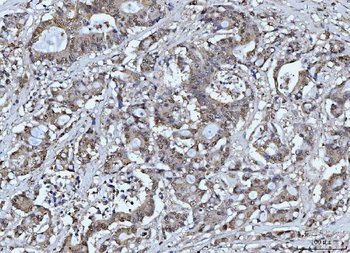

FEN1 Antibody

Catalog Number: orb193665

| Catalog Number | orb193665 |

|---|---|

| Category | Antibodies |

| Description | FEN1 Antibody |

| Clonality | Polyclonal |

| Species/Host | Rabbit |

| Conjugation | Unconjugated |

| Reactivity | Human, Mouse, Rat |

| UniProt ID | P39748 |

| Tested applications | IF, IHC, WB |

| Antibody Type | Primary Antibody |

| Storage | Store at -20°C for long term preservation (recommended). Store at 4°C for short term use. |

| Note | For research use only |